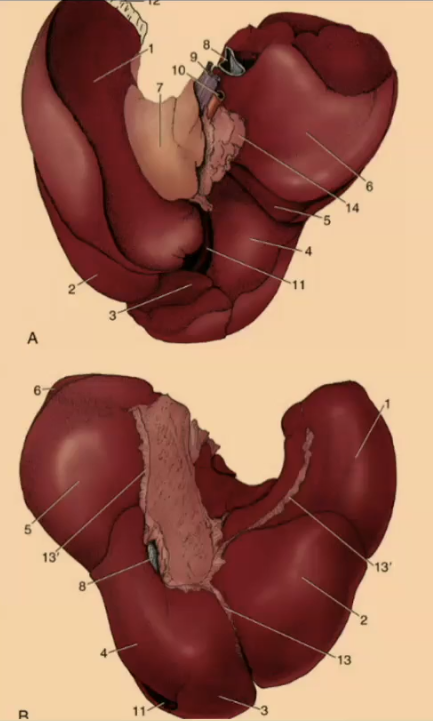

How many lobes are there to the liver?

4

What are the 4 lobes of the liver?

Left, Quadrate, Right, Caudate

#2?

Medial

#1?

Lateral

#3?

Quadrate

#4?

Medial

#5

Lateral

#6 & #7

Caudate